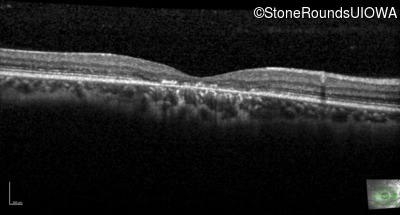

Optical Coherence Tomography - Left - 20/32 +1

Exemplar / OCT Stack

OCT Stack